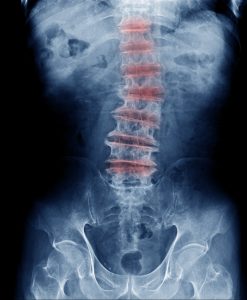

Degenerative Disc Disease refers to the symptoms of back and neck pain caused by wear and tear on a spinal disc. Spinal discs act like shock absorbers between the vertebrae of the spine. They help your back to to stay flexible so that you are able to bend and twist. In some cases Degenerative Disc Disease also causes weakness, numbness and hot, shooting pains in the arms and legs. It typically consists of a low-level chronic pain with intermittent episodes of more severe pain.

Painful Degenerative Disc Disease is most common in the neck and lower back as these areas of the spine undergo the most stress and motion making them more vulnerable.